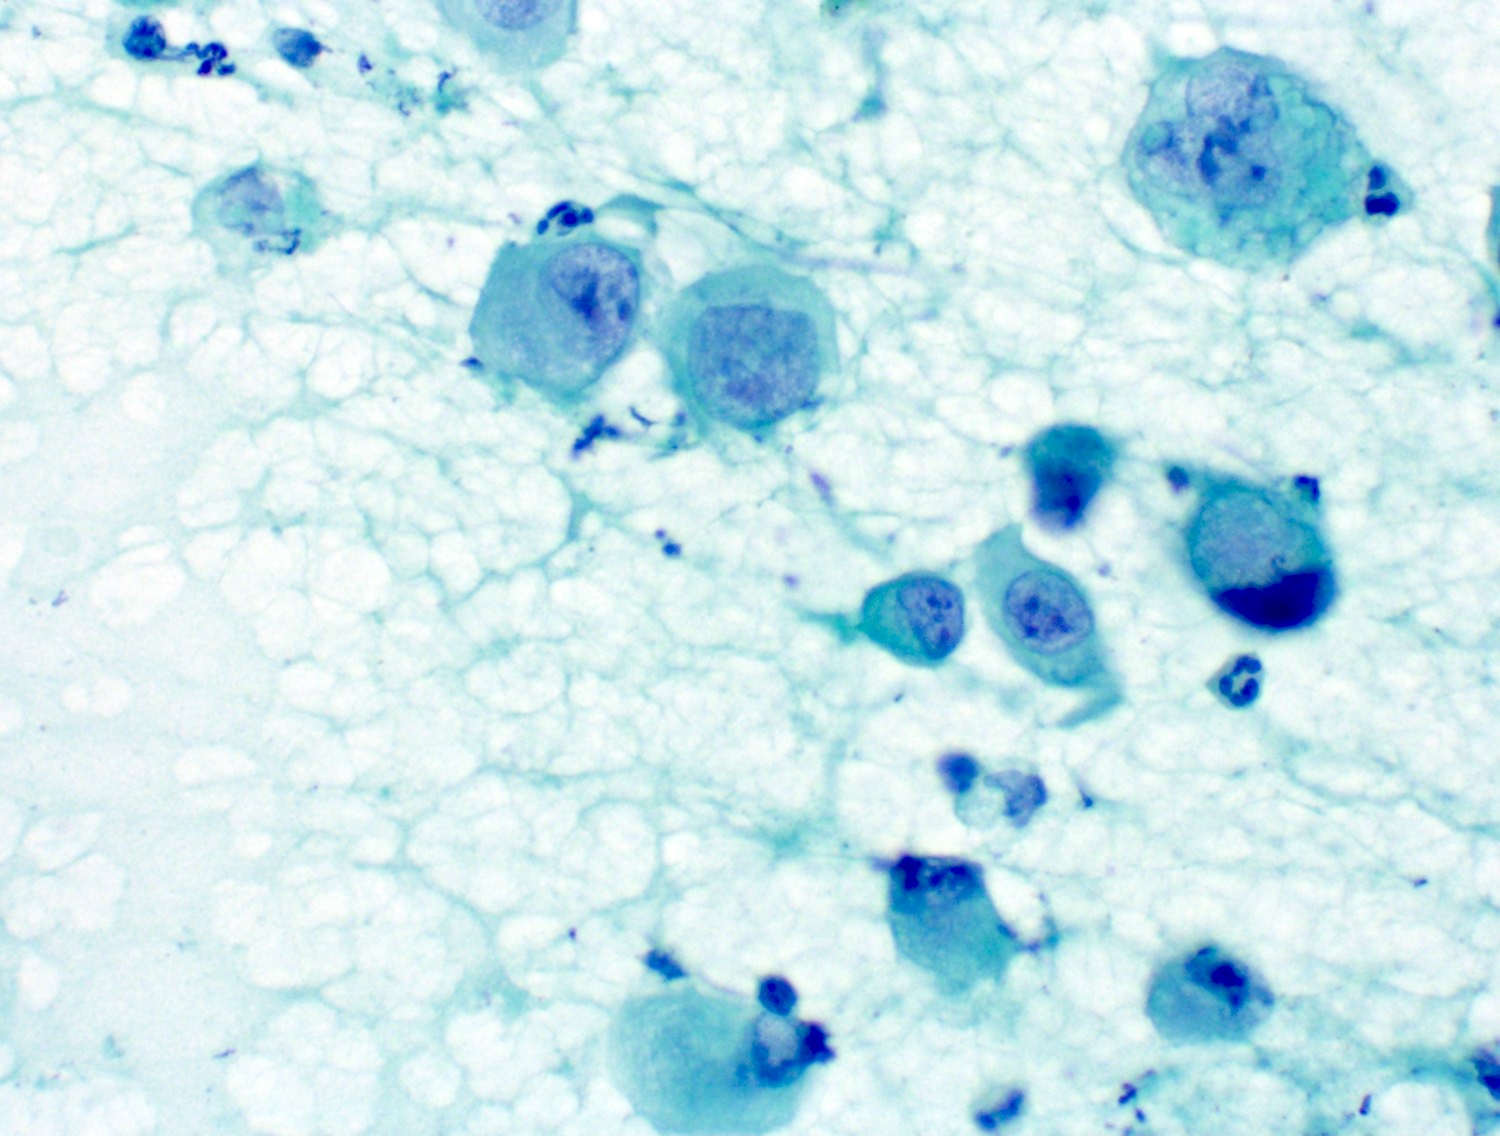

Cytology description

- Well differentiated tumors have elongated cells, isolated cells, tightly cohesive clusters or syncytia (Cibas: Cytology - Diagnostic Principles and Clinical Correlates, 4th Edition, 2014)

- Poorly differentiated: large spindle shaped or epithelioid shaped pleomorphic nuclei (Cibas: Cytology - Diagnostic Principles and Clinical Correlates, 4th Edition, 2014)

- Rhabdoid forms may occur in some epithelioid angiosarcomas (Cibas: Cytology - Diagnostic Principles and Clinical Correlates, 4th Edition, 2014)

- Discohesive epithelioid cells with nuclear pleomorphism and occasional spindle cells (Cibas: Cytology - Diagnostic Principles and Clinical Correlates, 4th Edition, 2014)

- Variably cellular with necrotic background (Cancer Cytopathol 2016;124:659)

- Dense cytoplasm with cytoplasmic vacuoles containing red blood cells (erythrophagocytosis) or neutrophils (Cancer Cytopathol 2016;124:659)

- Endothelial wrapping suggestive of vascular channel formation (Cancer Cytopathol 2016;124:659)

- Large, atypical round to oval nuclei with prominent bar shaped nucleoli (Cancer Cytopathol 2016;124:659)

- Multinucleated tumor giant cells with atypical mitotic figures (Cancer Cytopathol 2016;124:659)

Cytology images